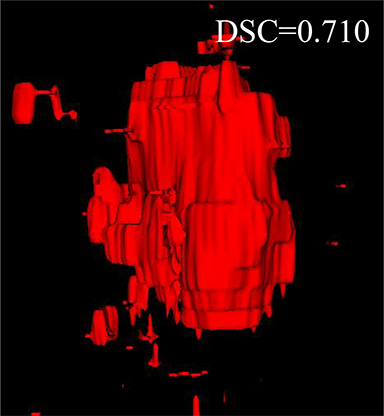

Comparison with related works. Table 1 reports the values of , and for different methods. Predicted masks of different methods are illustrated in Figure 9 and Figure 10, which respectively present results in 2D and 3D images. Through comprehensively analyzing these results, the proposed MMFNet actually have the following properties:

(i) It directly fuses 3D MRI images rather than 2D slices. Thus, it can effectively use meaningful information from neighboring slices of MRI to realize NPC segmentation. As shown in Table 2, MMFNet can bring , and improvements in and compared to the best method based on 2D images (Multi-modality patch-based CNN). And Figure 10 shows that 3D-based methods have less isolated regions (false positives) than 2D-based ones.